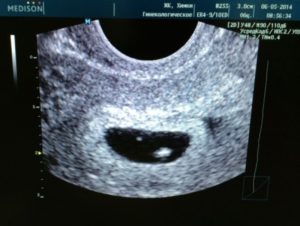

Доктор фиксирует на экране плодное яйцо — как выглядит оно, какие размеры имеет — и отмечает отсутствие эмбриона.

Если женщина сомневается в компетентности врача, то может пройти повторное обследование через несколько дней. При этом необходимо учитывать интенсивность выделений и исключить кровотечение. Если и повторная диагностика показывает плодное яйцо без эмбриона пустого кольца при этом видно на экране — то сомнения в предположении анэмбрионии нет.

Так на УЗИ выглядит пустое плодное яйцо.

Узи диагностика

Только на шестой неделе беременности пустое плодное яйцо можно диагностировать с помощью УЗИ. Оно проводится в любом случае, чтобы определить месторасположение плода, а также исключить внематочную беременность.

Определить анэмбрионию по УЗИ можно не ранее 5-6 недель беременности, но и на этом сроке могут быть ошибки.

Диагностических критериев для идентификации анэмбрионии довольно немного. Достоверным признаком отсутствия развивающегося эмбриона в плодном яйце является визуализация при помощи ультразвукового исследования.

Конечно же, бывают случаи, что беременность в плодном яйце есть, но не видно эмбриона. Эта ситуация относится к малым срокам.

Однако, если нет эмбриона в плодном яйце 6 недель или нет эмбриона в плодном яйце 7 недель, то тут стоит говорить о патологии.

Явным признаком неблагоприятного развития беременности, которые указывают на такую патологию, как анэмбриония, является отсутствие желточного мешка при размере плодного яйца 18,25 мм, а при его размере свыше данных показателей — отсутствия самого эмбриона. Если плодное яйцо 5 недель, то эмбриона не видно, но если нет эмбриона в плодном яйце 8 недель, то в этом случае можно смело говорить о наличии такой патологии. Предположить о неразвивающейся беременности можно косвенно по значениям уровня хорионического гонадотропина человека. Конечно же, ХГЧ будет иметь тенденцию к росту. Этим и отличаются анэмбриония и замершая беременность, при которой уровень ХГЧ будет стремительно падать вниз.

Согласно данных УЗИ, выделяют два типа анэмбрионии. Первый характеризуется тем, что диаметр плодного яйца не превышает 25 мм, размеры матки соответствуют 5–7 неделе беременности, но отстают от реального срока. При втором типе яйцо растет с нормальной скоростью и к 2,5 месяцам достигает 50 мм, однако не визуализируется ворсинчатый хорион.